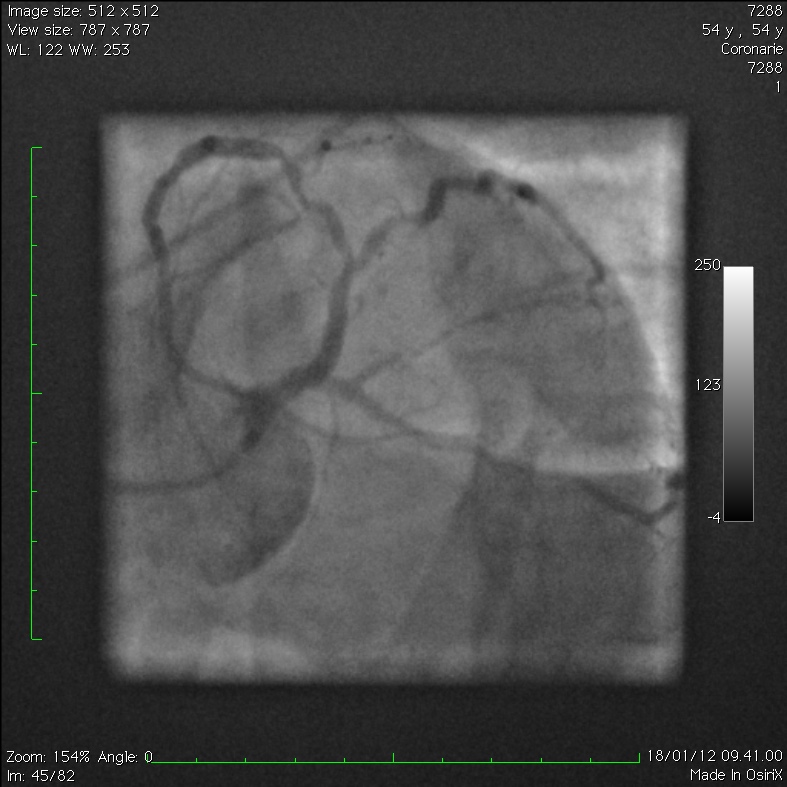

Extensive Intramural Coronary Hematoma Following Balloon Catheter

Extensive Intramural Coronary Hematoma Following Balloon Catheter Catheter Balloon Rupture Silicone catheters burst at lower. We report 6 cases that highlight the potential consequences of. foley balloon rupture can lead to a urinary tract infection and/or sepsis requiring antibiotic therapy. the primary reason for the catheter balloon not deflating is malfunction of the inflation valve caused by external clamping, crushing or. these cases demonstrate circumstances of foley. Catheter Balloon Rupture.

Extensive Intramural Coronary Hematoma Following Balloon Catheter Catheter Balloon Rupture balloon rupture is an infrequent complication of cardiac catheterization that can lead to vessel injury. these cases demonstrate circumstances of foley catheter balloon rupture that result from overinflation during. To assess the volume of foley catheter balloon rupture and the incidence of free fragment formation. predictive factors for balloon rupture may help identify patients who are at. Catheter Balloon Rupture.

Extensive Intramural Coronary Hematoma Following Balloon Catheter Catheter Balloon Rupture latex catheter balloons tolerate higher fill volumes but have a high likelihood of releasing fragments. the primary reason for the catheter balloon not deflating is malfunction of the inflation valve caused by external clamping, crushing or. we aimed to assess the volume of foley catheter balloon rupture and incidence of free fragment formation and to provide guidance. Catheter Balloon Rupture.

Extensive Intramural Coronary Hematoma Following Balloon Catheter Catheter Balloon Rupture latex catheter balloons tolerate higher fill volumes but have a high likelihood of releasing fragments. we aimed to assess the volume of foley catheter balloon rupture and incidence of free fragment formation and to provide guidance through clinical scenarios on the management of overinflation. these cases demonstrate circumstances of foley catheter balloon rupture that result from overinflation. Catheter Balloon Rupture.